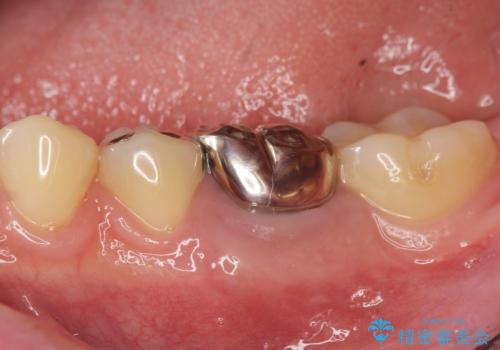

- 銀歯が揺れる、噛むと痛い、と治療を希望され来院されました。

銀歯・レジンコアを除去したところ、薄い残存歯質に亀裂が入り、保存が難しい状況が認められました。